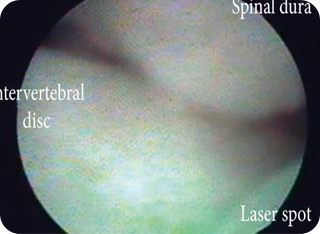

내시경 신경성형술

내시경을 이용해 신경 주변의 유착을 제거하고 약물을 주입하는 시술입니다.

절개 없이 진행되며, 만성적인 신경 통증이나 수술 후 통증 증후군에 효과적입니다.

• #허리디스크(추간판 탈출증)

• #척추관협착증

• #수술 후 통증 증후군